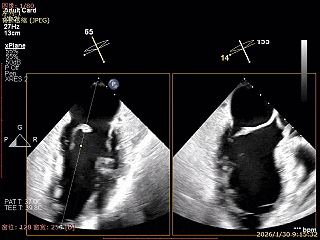

房间隔穿刺高度4.1cm

SGC穿房间隔进入左房

第一枚XTR进入左房

在1区进行轨迹测试和Orientation调整

将调整好的夹子移动至3区下左室

在左室打开夹子确认Orientation

捕捞瓣叶,确定瓣叶瓣尖稳定插入夹臂后,Gripper Down

Gripper Down后Bouncing明显

夹子关紧后,前后叶受限明显

夹子内侧反流消失

夹子外侧残余脱垂与反流

3D Enface下组织桥稳定残余外侧前叶脱垂

3D Enface上彩可见夹子内侧无反流,残余外侧反流